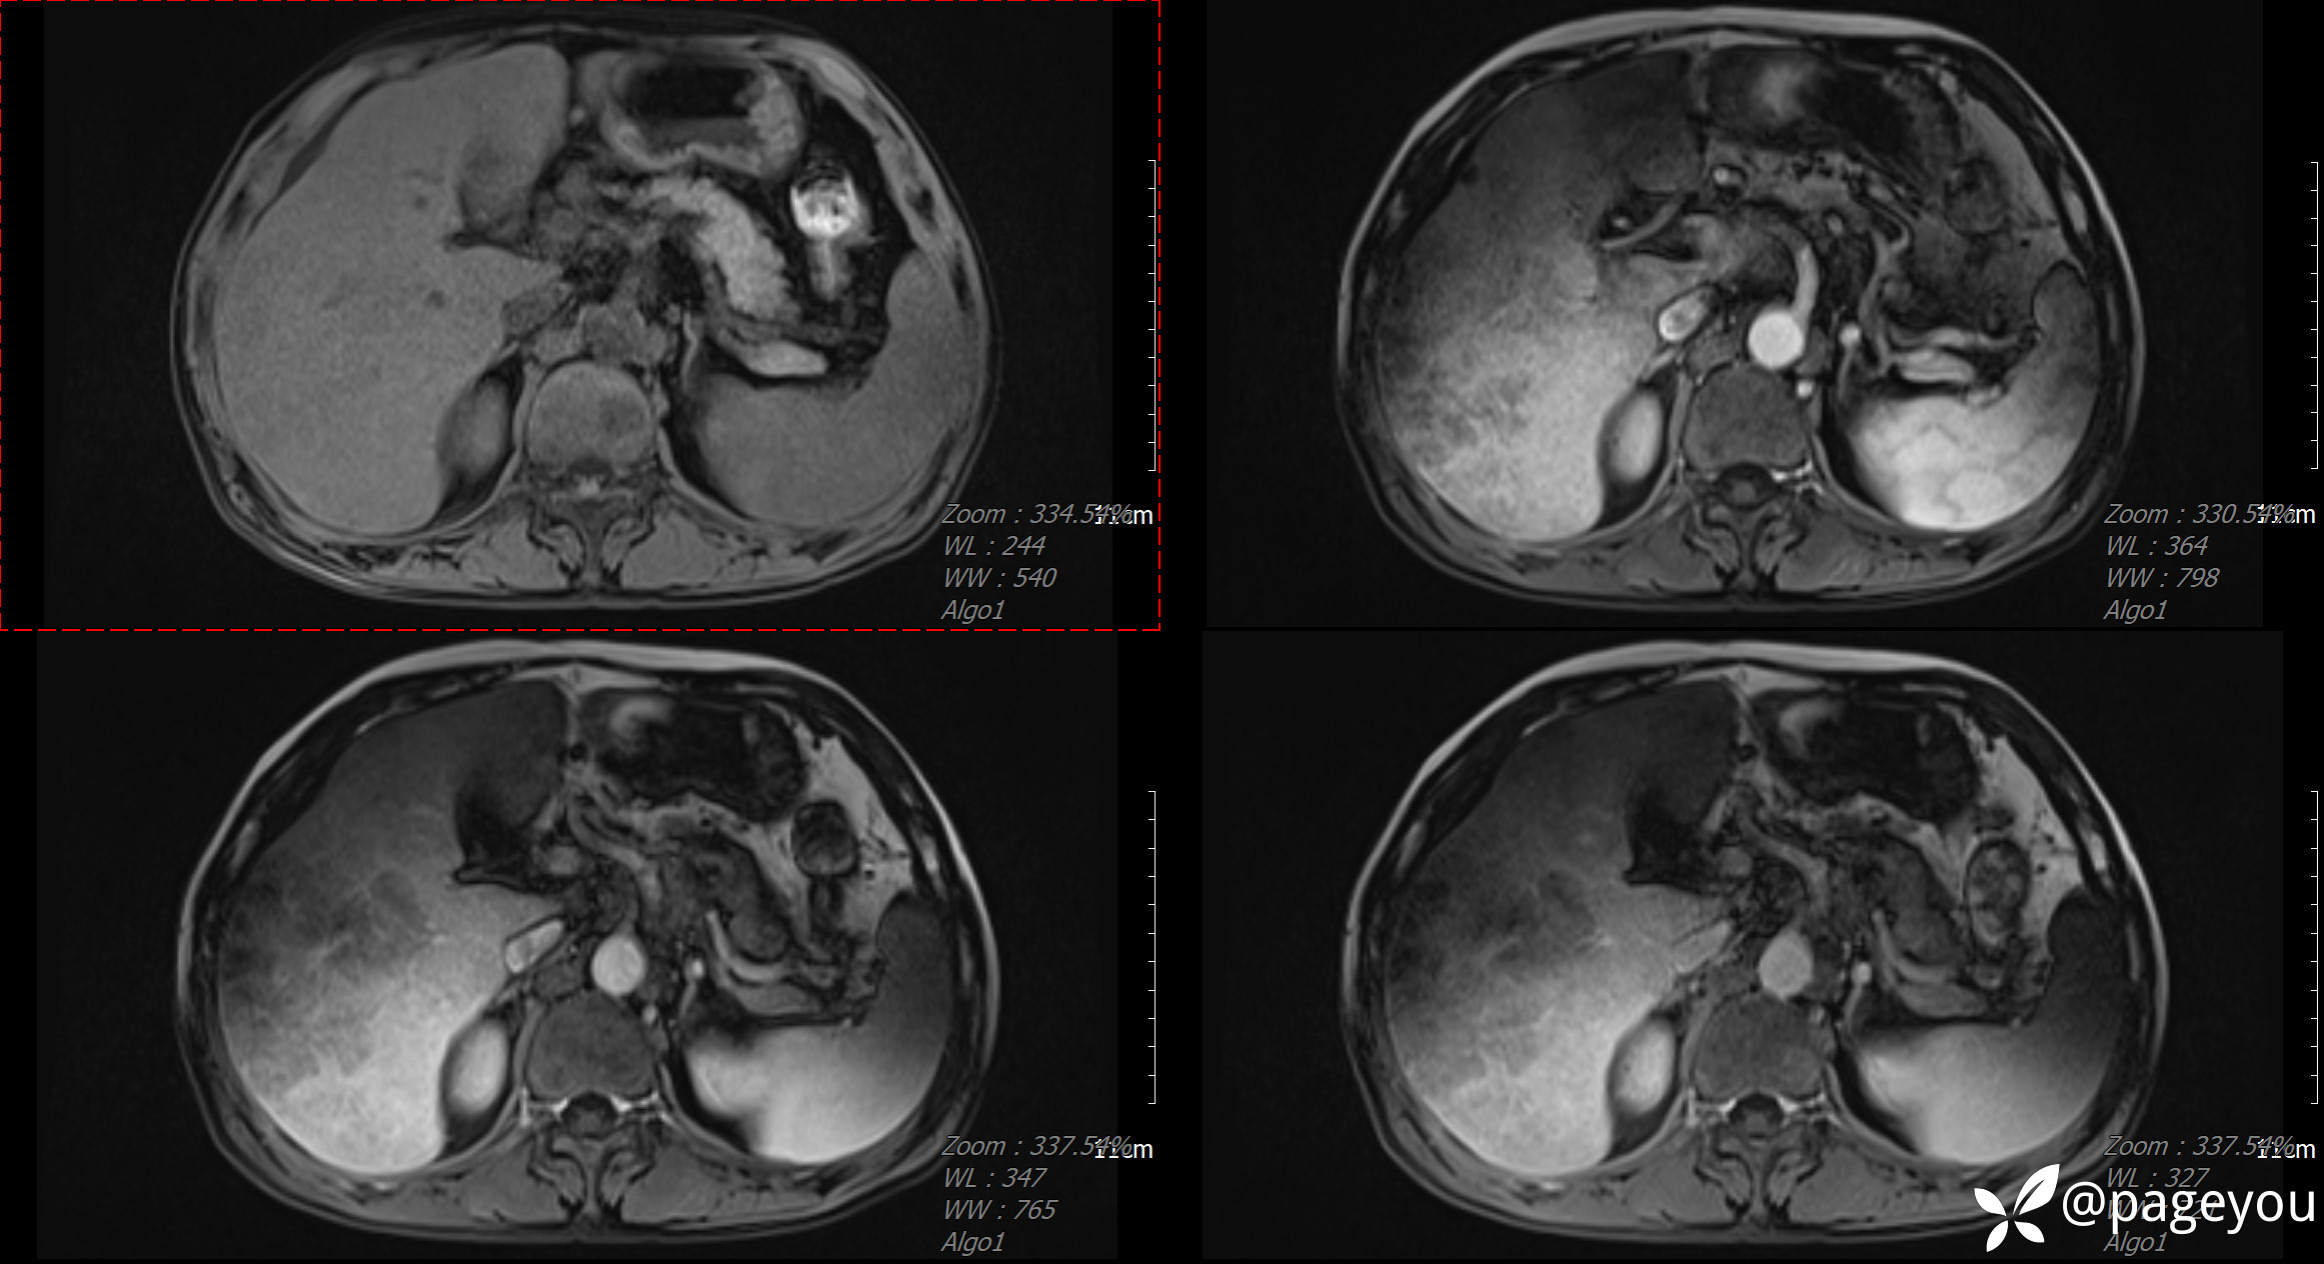

CT检查:

MRI检查: